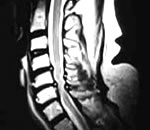

Мне 45 лет, нахожусь в климактерическом периоде (патологический климакс, выматывает ужасно на фоне имеющихся заболеваний - недостаточность мозгового кровообращение на фоне остеохондроза шейного (4 протрузии и спондилоартроз) и грудного отделов позвоночника (деформация тела Тh8 позвонка (снижение в высоте позвонка), остеохондроз, остеофиты); гипертоническая болезнь 2 ст., тахикардия, хронический тонзиллит; диффузный зоб 2 ст. (ТТГ - 1.63 мМЕ/мл (норма 0,25-5,0 мМЕ/мл); Т3 - 4,42 пмоль/л (норма 4-8.3 пмоль/л); Т4 - 15,02 пмоль/л (норма 9.0-20.0 пмоль/л); антитела к тиреопероксидазе 6,5 Ul/ml (норма до 50 Ul/ml)), хотя до климакса Т4 иногда повышался), цикл 24-70 дней (чем дольше нет, тем лучше (спокойней, комфортней)!). Принимаю "Абьюфен".

МРТ шейного и поястнично-крестцового отдела. Заключение(что как бы основное) – остеохондроз (дегидрация пульпозных ядер,экструзии-протрузии, грыж нет, в пояснице умеренная компрессия корешков и т.д). Давление – низкое(110-120/ 65-70). Анализы крови, мочи, кардиограмма – в норме. Глистов нет. Узи органов брюшой полости . Комментарий УЗИста: есть небольшие вопросы, но как бы с таким многие живут ( песок в почках, небольние кисты в почке и печени(через 6 мес. перепроверить), желчный увеличен, выход деформирован, застойная желчь и т.д. щитовидка в норме, поджелудочная не увеличена.) Дуоденальное зондирование показало небольшие эррозии в желудке, рефлюс, повышен. кислотность. После этого был сделан анализ на хеликобактер - не обнаружен.